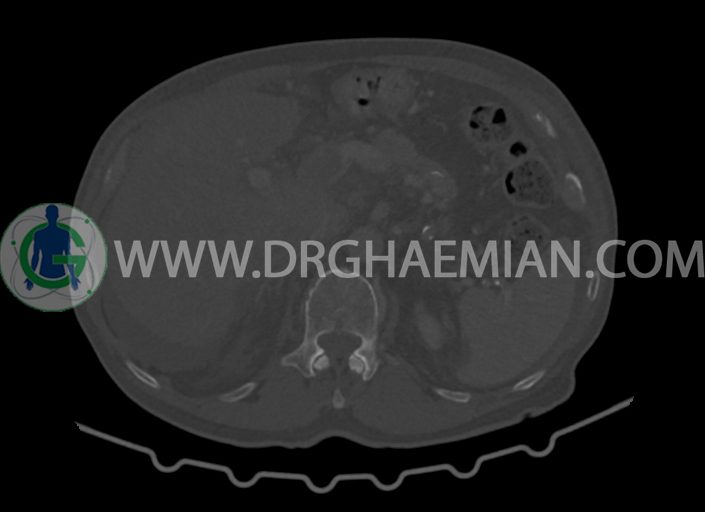

در سی تی اسکن اسپیرال شکم و لگن با کنتراست خوراکی و وریدی (مولتی دیدکتور 16 با مقاطع ظریف و بازسازی های ساژیتال و کرونال) :

کلیه ها کنتراست را ترشح کرده اند و نمای سیستم پیلوکالیسیل و حالب دو طرف نرمال است .

–پروستات با دیامتر عرضی بزرگتر از نرمال 63mm همراه با بالجینگ به کف مثانه

-مایع آسیت با حجم Mild در ساب فرنیک دو طرف ، ساب هپاتیک و ساب اسپلنیک و اینترلوپ لگنپ

-کیست های کورتیکال ساده در هر دو کلیه به بزرگترین قطر 27mm در سمت چپ (بوسنیاک 1)

-مثانه با جدار ضخیم و نامنظم